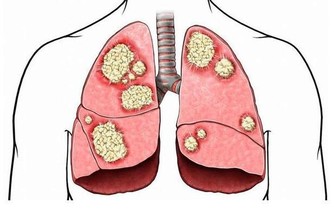

有對長壽的夫妻,丈夫不菸不酒愛運動,是個瘦子,太太則完全相反,是個胖子,兩人同時得到流感,變成肺炎!結果太太幾天就恢復出院,丈夫卻住進加護病房...為甚麼會這樣呢?醫生解釋,因為瘦,膽固醇低,罹患肺炎時,身體沒有儲備能量,容易有併發症。

現代人飲食五花八門,容易營養過剩,大家普遍會認為胖不好!但高齡醫學專家表示,「體重稍微肥胖」者(BMI值23-25間)其實死亡率比較低,體重過輕的人因為營養失調,一旦染病就容易有併發症。稍微胖一點,才有本錢對抗疾病,不須太忌口,只要維持好飲食習慣,避免三高(高血壓、高血糖、高血脂)就可以。